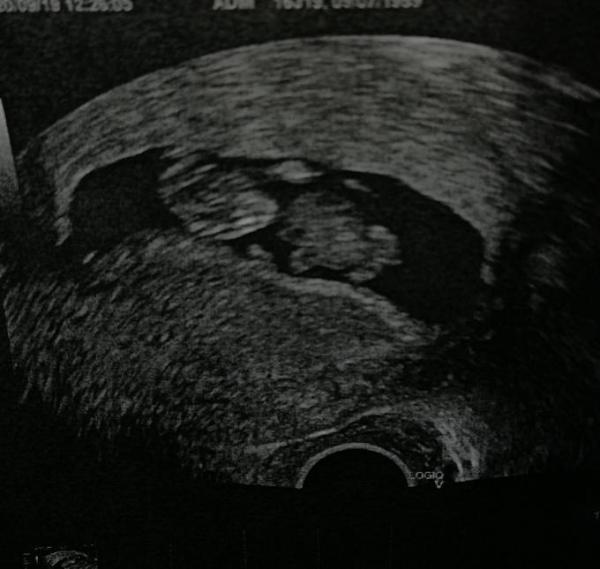

Heute hatte ich endlich wieder einen Termin und es sieht alles super aus, ich könnte einfach die ganze Welt umarmen, so haben wir es dann auch unseren Jungs mitgeteilt, dauerte zwar etwas bis sie das mit den T-Shirts und dem US Bild verstanden haben aber umso größer war die Freude, es ging gleich los mit Namensüberlegungen und so... einfach ein sehr erfolgreicher Tag. Jetzt kann ich hoffentlich wieder etwas ruhiger schlafen und ab nächster Woche weiß es dann eh jeder, da der kleine das mit dem Familiengeheimnis nicht so wirklich ernst nimmt

Bild zu Einfach total happy - Forum für April - Mamis